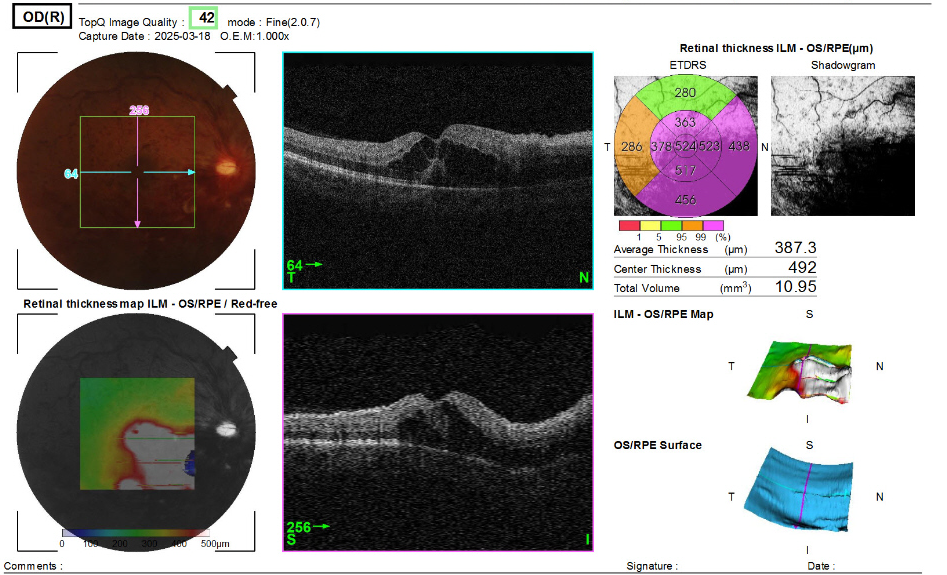

오른쪽 OCT 촬영결과

2. 두 번째 이미지 (OCT 촬영) 분석

- 황반부 중심두께(Center Thickness): 492μm → 정상보다 두꺼움

(정상 망막 두께는 약 250~300μm) - 망막 단층 이미지에서 중심부 종창(부종) 확인됨 → 황반부종(Macular Edema) 가능성

- 보통 당뇨망막병증, 황반변성, 망막정맥폐쇄(Retinal Vein Occlusion, RVO) 등의 질환과 관련됨.

- 망막 표면의 불규칙성 및 일부 액체(저반사 영역) 확인 → 삼출물 혹은 낭포 가능성

- 망막하액(subretinal fluid) 또는 낭포형 황반부종(cystoid macular edema, CME)일 가능성이 있음.

- ETDRS(황반부 분석 그래프)에서 중심부(524~523μm)와 주변부에서 두께 증가 패턴이 보이며, 이는 중심성 황반부종(Central Macular Edema) 의 전형적인 소견.

현재 황반부의 두께 증가 및 부종이 관찰되므로 황반변성, 망막정맥폐쇄(RVO) 등과 관련된 질환 가능성이 있음.